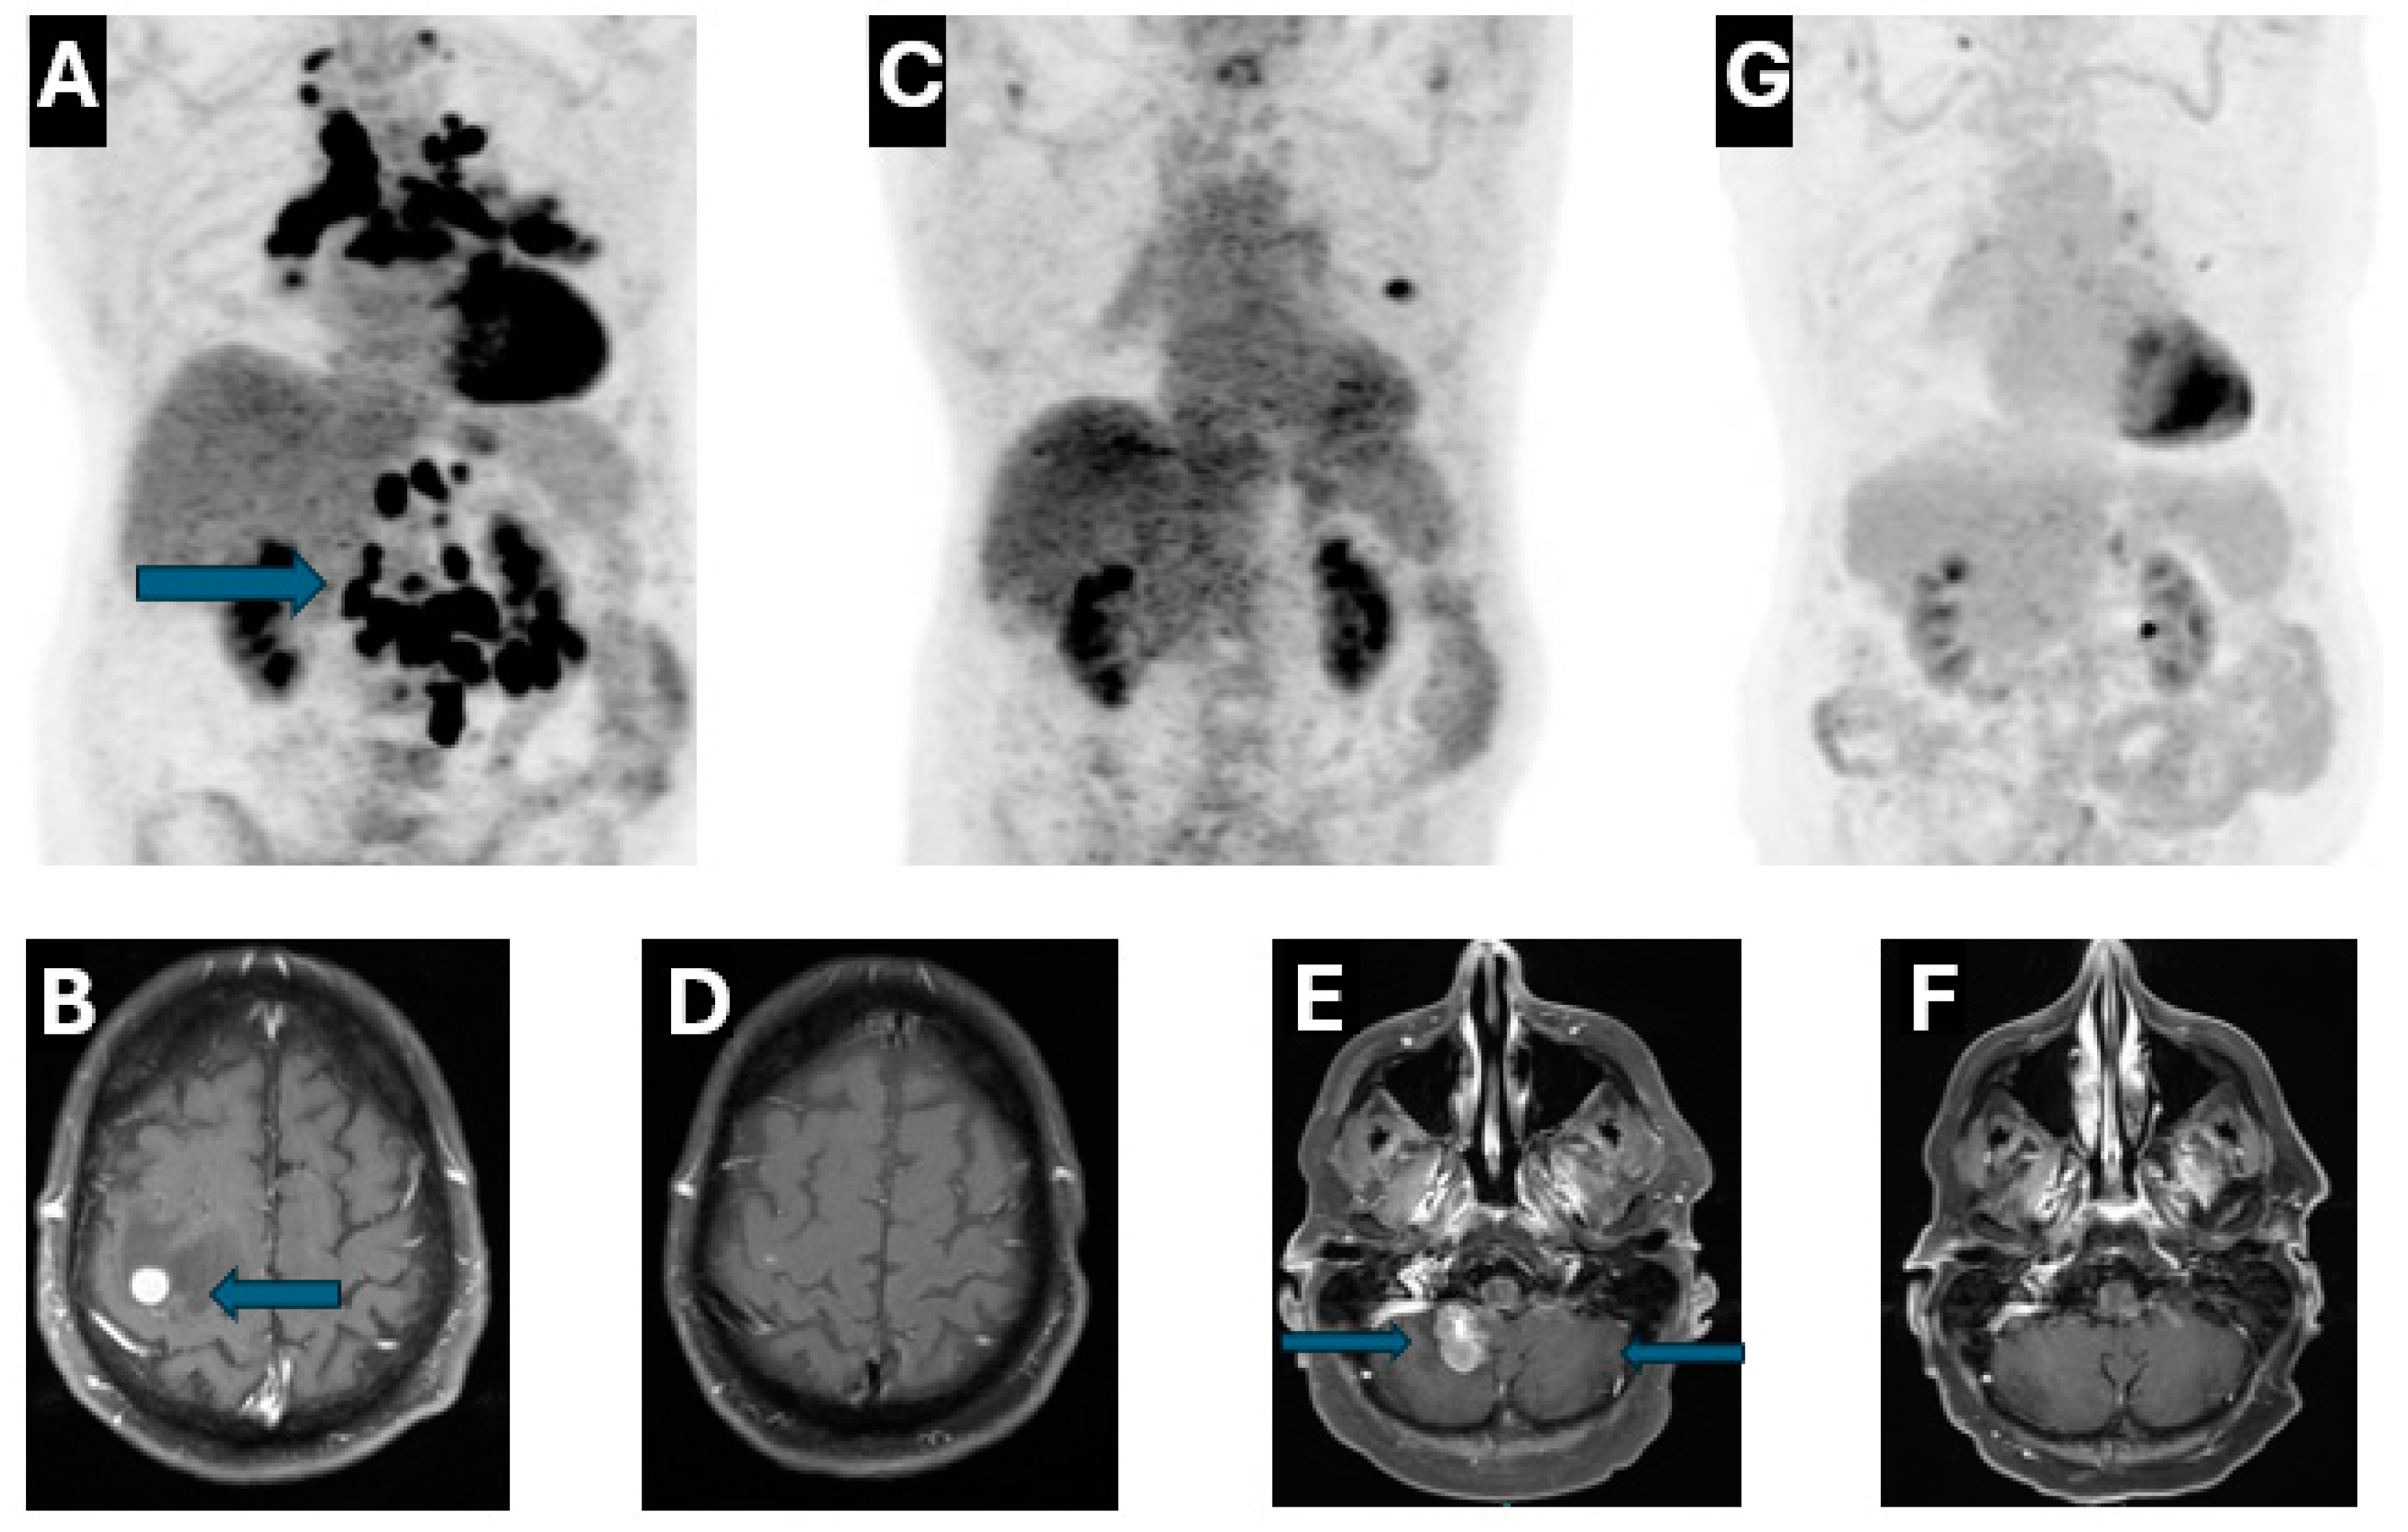

A 72-year-old male, a former smoker with a five-year smoking history, originally presented to the emergency department (ED) with progressively worsening nausea, vomiting and cough with dyspnea in November 2019, computed tomography (CT) chest angiography showed a 1.7 cm spiculated nodule in the left upper lobe. CT abdomen and pelvis further demonstrated extensive metastasis to the mediastinal, cervical, retroperitoneal, and mesenteric lymph nodes. The patient reported melena and was noted to have severe anemia with hemoglobin to 6.7 g/deciliter which prompted an esophagogastroduodenoscopy (EGD) with biopsy of the third portion of the duodenum. Biopsy revealed poorly differentiated adenocarcinoma, positive for TTF-1 and Napsin A, highly consistent with lung origin, and ruling out other potential sites. Outpatient Positron Emission Tomography (PET)-CT confirmed the CT findings and demonstrated FDG-avidity in the duodenum, supporting the diagnosis of lung cancer with duodenal metastasis (Figure 1A). Subsequent Magnetic resonance imaging (MRI) Brain was ordered due to progressive left arm weakness, which confirmed the correlation of symptomatic brain metastases with four enhancing lesions measuring up to 1 cm (Figure 1B). He completed stereotactic radiosurgery (SRS) to brain metastases and regained full motor and sensory function in the left arm. Next-generation sequencing (NGS) revealed METex14 skipping deletion with a programmed death-ligand 1 (PD-L1) > 80%. Given the great tumor burden and lack of effective targeted options at that time, the patient received chemoimmunotherapy combination with carboplatin/pemetrexed/pembrolizumab for four cycles. Repeat imaging studies in April 2020 exhibited a remarkable response both intracranially and extracranially (Figure 1C,D).

Figure 1.

(A), PET-CT: Baseline tumor burden including duodenal metastasis (12/2019); (B), MRI brain: Brain metastasis at the diagnosis (12/2019); (C), PET-CT: 3 months after chemoimmunotherapy (4/2020); (D), MRI brain: 3 months after chemoimmunotherapy (4/2020); (E), MRI brain: Baseline with cerebellar metastasis and LMD (6/2022); (F), MRI brain: 6 weeks after chemotherapy and tepotinib (7/2022); (G), PET-CT: 15 months after re-starting tepotinib (6/2024).

The patient developed ataxia in May 2022, MRI Brain demonstrated a new lesion at the right cerebellum with evidence of leptomeningeal disease (LMD) (Figure 1E). He immediately began chemotherapy with carboplatin/pemetrexed/bevacizumab in early June 2022, as TKI was not immediately available. Tepotinib was added to the regimen approximately two weeks later. An MRI brain scan six weeks later showed an excellent therapeutic response with significant size reduction in the right cerebellar lesion and resolution of leptomeningeal enhancement (Figure 1F). At that time, carboplatin/pemetrexed was discontinued due to severe fatigue and cytopenia, while bevacizumab maintenance in combination with tepotinib was continued. The patient gained approximately 20 pounds despite the use of aggressive diuretics. CT chest/abdomen/pelvis in September 2022 revealed no evidence of disease, but development of mild pericardial effusion and bilateral pleural effusion. The fluid retention could be attributed to multiple factors including side effects of tepotinib, left mitral valve regurgitation due to chordal rupture and renal insufficiency. Thus, both tepotinib and bevacizumab were held from September to December 2022. The patient underwent two ultrasound guided left thoracenteses between November and December 2022 with pleural fluid cytology negative for malignancy. Bevacizumab/tepotinib was resumed in December 2022, but tepotinib was held again due to ~30-pound weight gain despite re-starting with a reduced dose at 225 mg daily. The patient underwent a repeat mitral valve clip in February 2023. With clinical improvement, tepotinib 225 mg daily was restarted in May 2023; both MRI brain and PET-CT in June 2023 demonstrated no evidence of disease. Bevacizumab was discontinued in June 2023, and the patient has remained on tepotinib monotherapy ever since. Of note, the patient ran out of tepotinib for three months due to insurance issues and was restarted in March 2024. The patient continues to have stable moderate fluid retention requiring compression stockings. Both MRI Brain and PET-CT continue to exhibit a great response without convincing evidence of progression of disease (Figure 1F,G). See Figure 2 for a timeline of clinical milestones over the 5-year course of treatment.